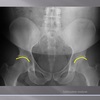

AP LUMBOPELVIC LANDMARKS A-P lumbopelvic view

femur heads

110

A-P lumbopelvic view

superior iliac crests

111

lateral iliac crests

112

ischial tuberosities

113

s2 tubercle

114

pubic/pubic symphysis

115

sacral grooves

116

lateral aspect of sacrum

117

medial aspect of ilium

118

obturator foramen

119

spinous processes

120

supeiror endplate tips

121

lumbar pedicle shadow